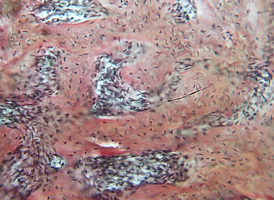

Морфологическое и лабора-торное обоснование приме-нения комбинированных трансплантатов при костной пластике челюстей

Экспериментальное исследование. Изучение морфогенеза после заме-щения дефектов нижней челюсти смесью лиофилизированной алло-спонгиозы и “аллогенного гидроксиапатита” в соотношении 1:1 и 3:1.

Экспериментальное исследование. Изучение морфогенеза после заме-щения дефектов нижней челюсти смесью лиофилизированной алло-спонгиозы и “аллогенного гидроксиапатита” в соотношении 1:1 и 3:1.